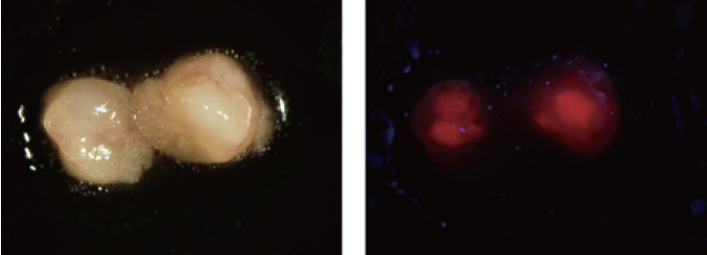

これらの問題を根本的に解決しうる方法が、5-アミノレブリン酸(5-ALA)を用いた診断である。体外から5-ALAを投与すると、正常細胞では、5-ALAは蛍光物質を認めないヘムに素早く代謝される。一方、がん細胞では、プロトポルフィリンIX(PpIX)と呼ばれる蛍光物質が蓄積する。この原理を応用しているのが、5-ALAを用いた診断法である。

① 暗い背景のなかに、赤く光る蛍光として検出できるため、今までのように形や色彩の変化がない小さながんでも発見できる。

▲5-ALAを用いたヒト胃がんリンパ節転移イメージング(左:白色光、右:蛍光)

1)5-Aminolevulinic acid(5-ALA)を用いたリンパ節転移診断

消化管癌の治療法選択には正確なリンパ節転移診断が不可欠である。通常リンパ節診断は摘出された病理標本を用いて行われるが、通常2~3枚の病理標本を作製し診断が行われるため、微小リンパ節転移は見逃される可能性がありその感度に限界がある1)。近年、蛍光を利用した腫瘍イメージングが臨床においても行われるようになり、特に5-Aminolevulinic acid(5-ALA)は、膀胱癌や脳腫瘍において原発腫瘍の診断に実際用いられている2)3)。5-ALAは、正常細胞では蛍光を認めないヘムにすばやく代謝されるが、腫瘍細胞では、porphobilinogen deaminaseの活性が高くferrochelatase の活性が低いため、蛍光物質であるprotoporphyrin IX (PpIX) が蓄積する。すなわち、5-ALAを生体に過剰投与し一定の時間を経て観察すると、PpIXが腫瘍細胞に選択的に残存し腫瘍の蛍光診断が可能となる。我々はマウス直腸癌モデルを用いて5-ALAの微小リンパ節転移診断能を検証したが、簡便な方法で高い診断能を有する事が示唆された(図1)4)。ヒト消化器癌においてもこの方法がリンパ節転移診断に有効であるデータを得ている。

図1 5-ALAを利用したリンパ節転移イメージング

A) BALB/cヌードマウスの直腸粘膜下にEGFP標識大腸癌細胞を注入し、直腸癌リンパ節転移モデルを作成。 B) マウスモデルに5-ALA(250mg/kg)を静注後、開腹。C) 大動脈周囲リンパ節を観察(左: 白色光、中央:EGFP蛍光、右:PpIX蛍光)。5-ALA-induced PpIX蛍光はEGFP蛍光に一致することがわかった。D) Macroconfocal imaging systemを用いた光学的断層像(C右図の点線内をスキャン)。リンパ管内に存在するPpIX蛍光陽性の微小癌病変(矢頭)も描出可能。E) マウス腹腔内転移リンパ節の蛍光寿命イメージング。大腸癌転移部位の蛍光寿命は周囲の正常組織より長いため(癌転移部位:約10 ns)、転移巣を描出可能(左:白色光、右:蛍光寿命イメージング)。Scale bar = 5 mm (A, B), 1 mm (C, D, E() 文献4より転載)